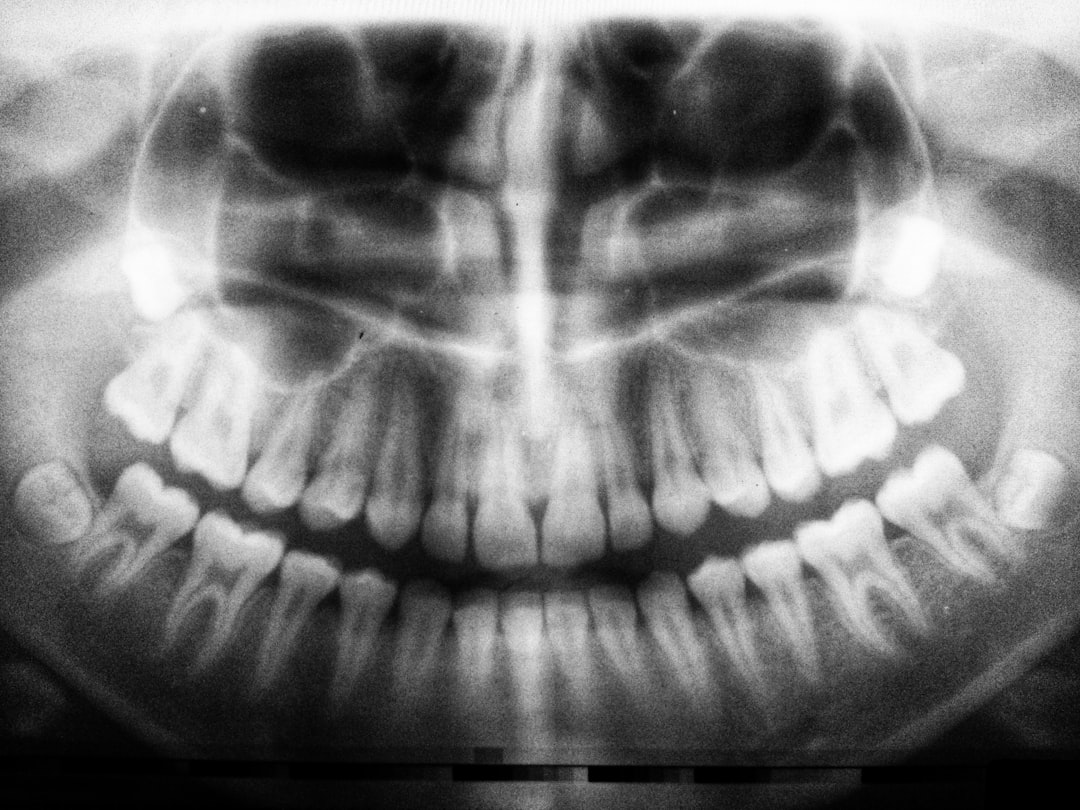

치료 과정은 일반적으로 진단, 수술 및 보철물 장착으로 나뉘며, 정밀한 3D 이미징과 컴퓨터 가이드를 통해 진행됩니다. 이로 인해 정밀도가 높고, 수술 시간도 단축될 수 있습니다. 적절한 환자 선정이 중요하며, 대부분의 경우, 이 방법은 기존의 임플란트보다 더 효율적입니다.

원데이 임플란트의 치료 일정은 통상적으로 하루에 완료되지만, 초기 진단 및 검사 과정은 포함되지 않다는 점을 유념해야 합니다. 진단을 위한 몇 번의 방문이 필요할 수 있으며, 실제 수술은 대개 1~2시간 정도 소요됩니다.